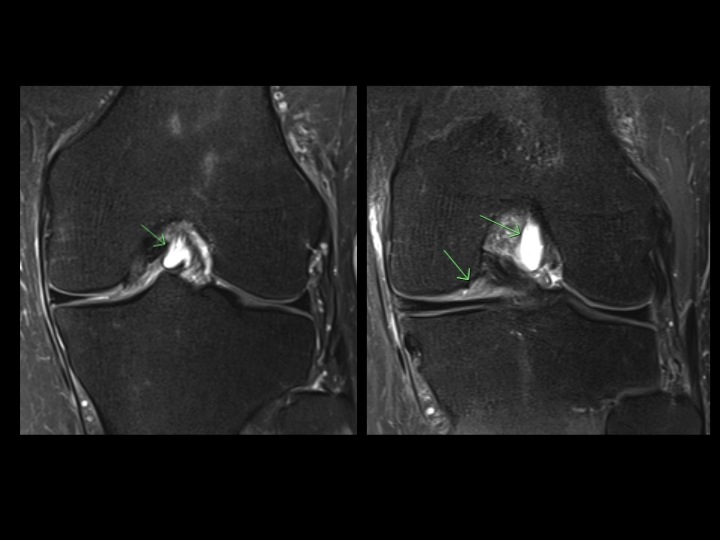

31 yr old male s/p injury 12 years ago with chronic pain

There is a chronic tear of the anteromedial bundle of the ACL with an intrasubstance ganglion. In the Obl Cor PD images it appears that there is complete or nearly complete tear of the anteromedial bundle, which is difficult to quantify in the Sag or axial plane. With this case being the exception, I rarely find that these Obl Cor images help much. What is the consensus? Do you use Obl Cor? Did you and have you abandoned it? Is it really worth the additional imaging time? Reference article.

anteromedial bundle of anterior cruciate ligament ( RID2782 )